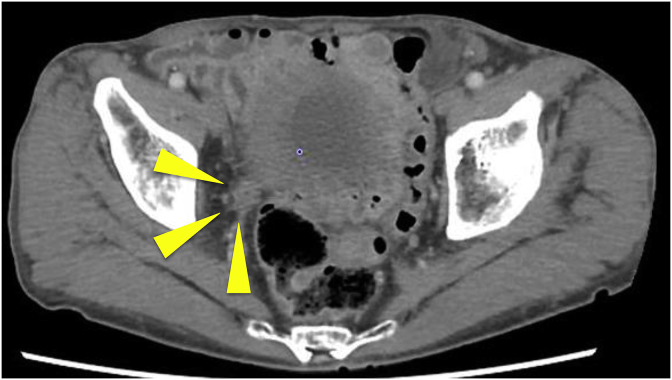

Fig. 1.

Computed tomography before pembrolizumab administration shows 30 mm right lower ureteral cancer.